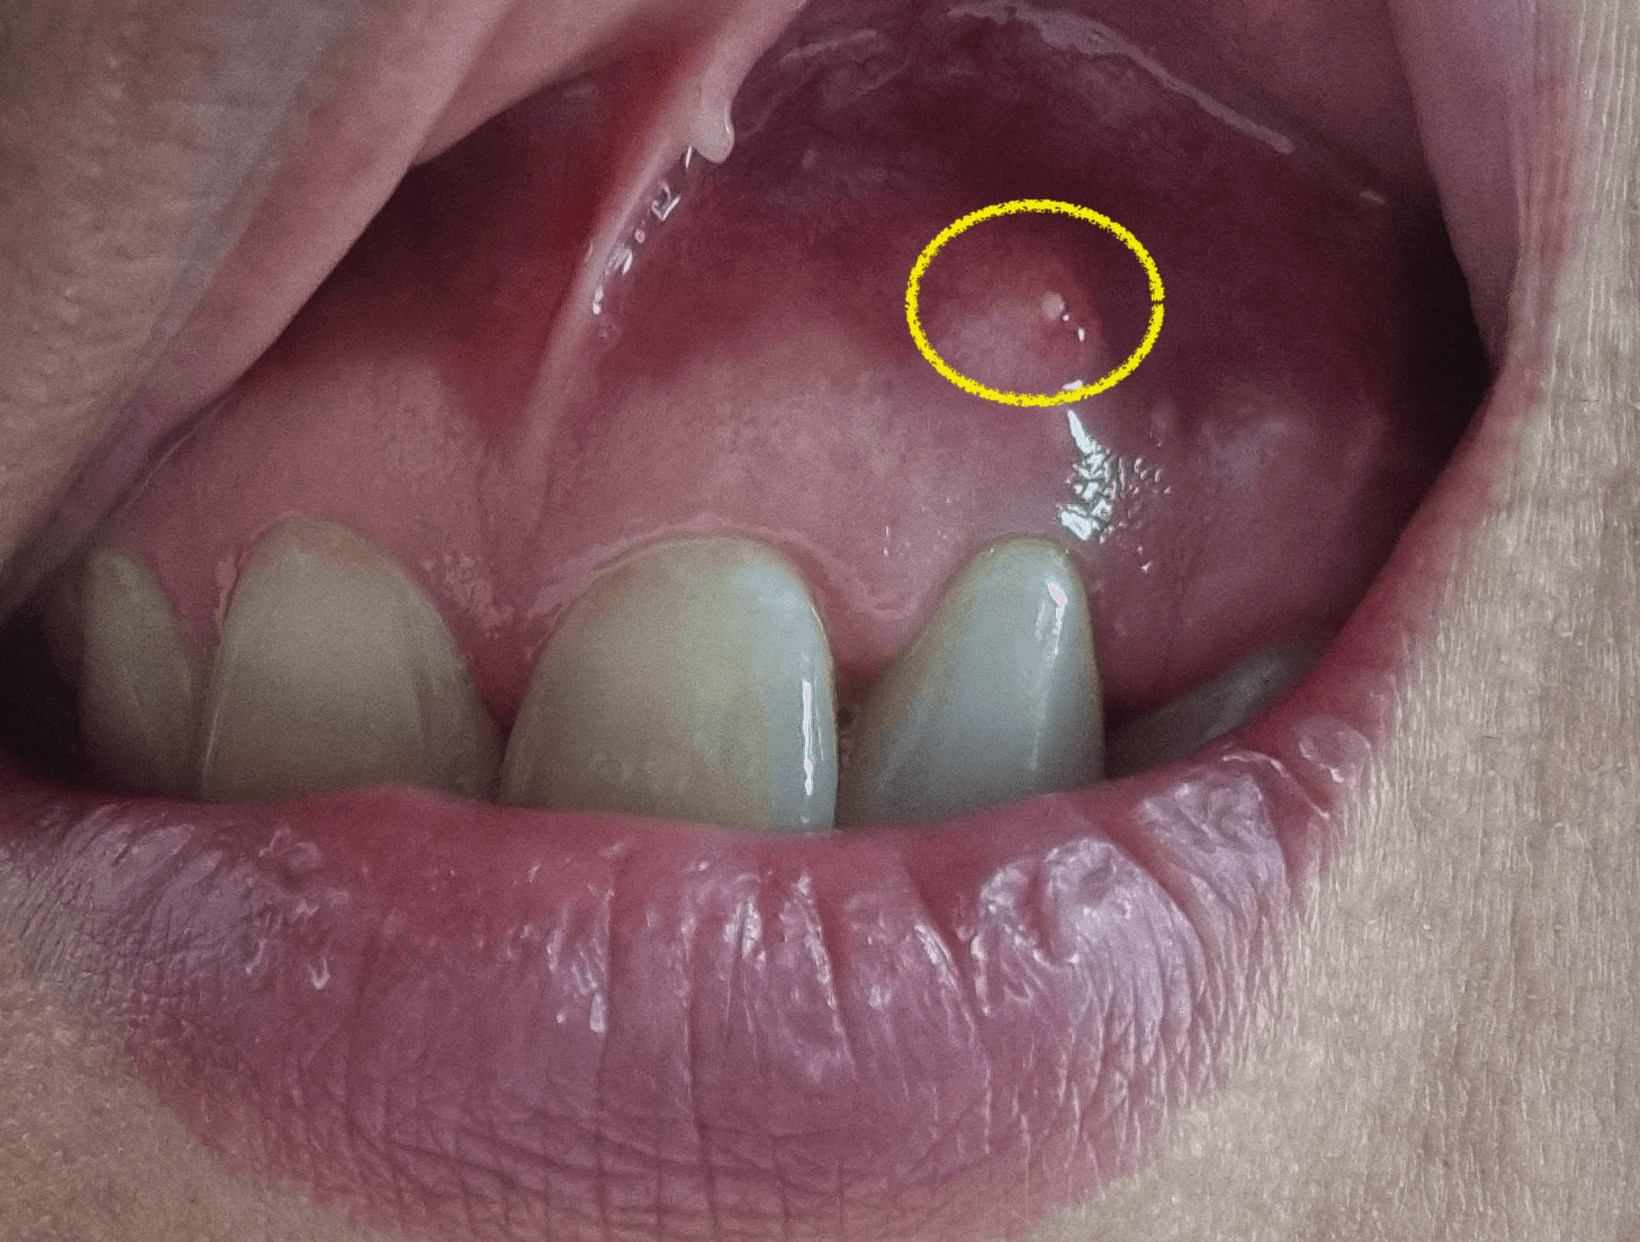

그래서 일단 병원에서 처방받은 염증약을 1주일 먹고 의사선생님이 재수술을 하면 가능성이 있겠다라고 이야기를 한다면 한번더 재수술을 해볼것이고, 재수술을 해도 잡기 힘들거라고 이야기 하는경우 일단 발치는 하지않고 몇달 정기점검을 받으면서 기존 다른 치아에 큰 무리가 없다면 몇년씩 그대로 유지하고 있던 사람들처럼 필자도 그렇게 해볼가 합니다.

제가 이전 앞니 염증이 생겼을때 8년정도 가지고 있었던거 같은데, 그때는 염증이 빠져나오지 못해 안에 있는 뼈를 녹였지만 지금같은 경우 염증이 생겨 부풀면 터져나오니 뼈를 녹일일은 없기에 바로 발치하지 않고 조금 무리하지 않게 사용해 보고 큰 이상이 없으면 유지해볼까 그런 생각도 있습니다.

치과의사 선생님 말씀으로도 그런분들이 꽤있고 몇년이 지나도 그대로 유지되는 분들이 많기 때문에 본인의 선택에따라 관리하면서 지켜보는것도 나쁜방법은 아니라고 이야기를 해주네요.

자 여러분들의 생각은 어떤가요, 저는 일단 처방전으로 받은 염증약을 먹고 치료가 가능하면 한번더 재수술을 할것이고 그게 아니라면 발치는 하지 않고 일단 통증이 심해지거나 다른 치아에 무리가 되면 그때 발치를 할까 생각중입니다. 최대한 사용하고 있는 치아를 오랜기간 사용후 무리가 생길때 그때 발치할까 생각하네요.